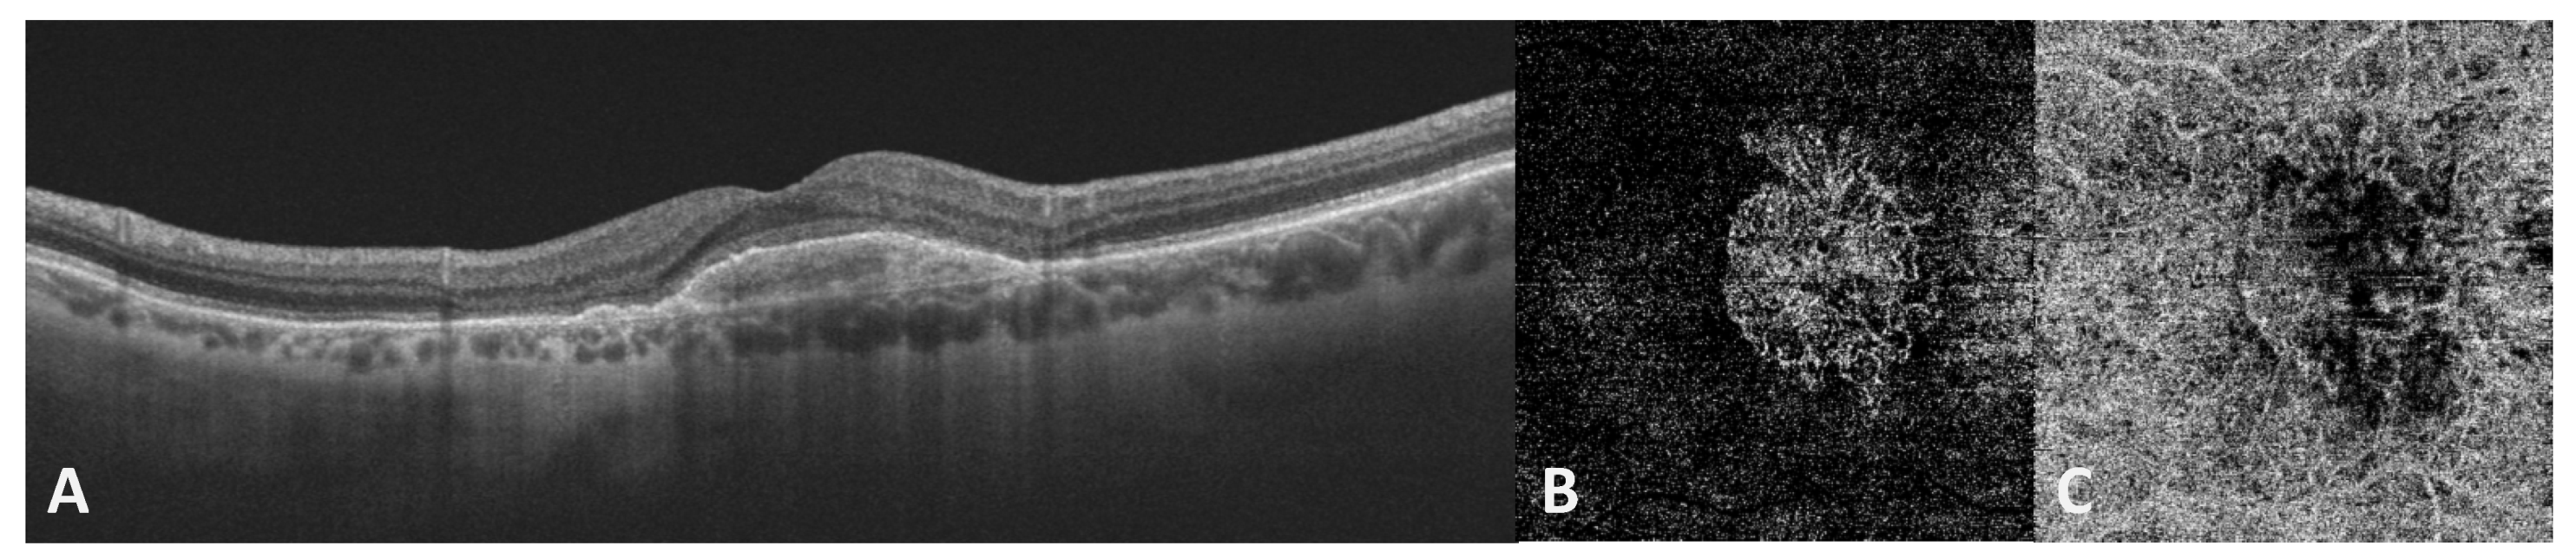

- Vujosevic, S.; Toma, C.; Villani, E.; Muraca, A.; Torti, E.; Florimbi, G.; Pezzotti, M.; Nucci, P.; De Cillà, S. Quantitative choriocapillaris evaluation in intermediate age-related macular degeneration by swept-source optical coherence tomography angiography. Acta Ophthalmol. 2019, 97, e919–e926. [Google Scholar] [CrossRef]